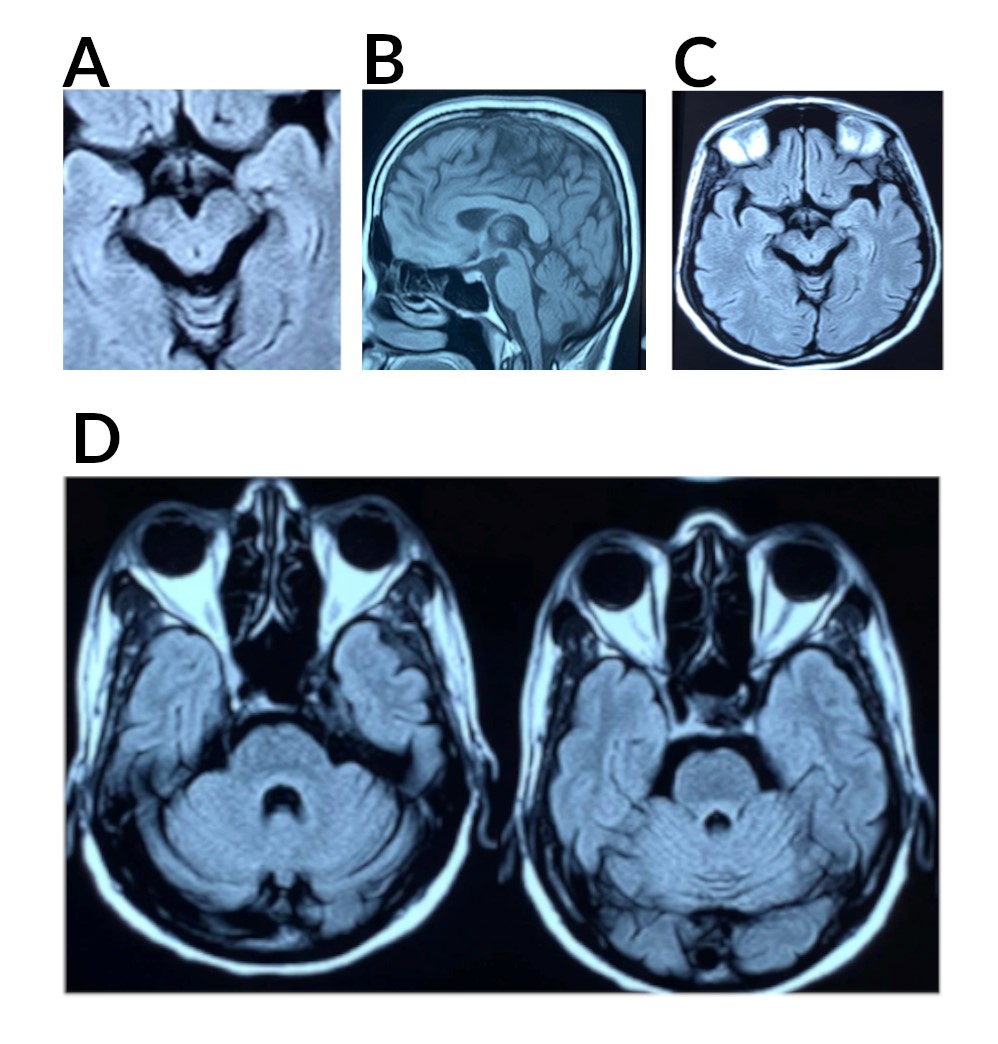

Results: Routine metabolic, autoimmune, and paraneoplastic profiles were normal, and MRI showed cerebellar and midbrain atrophy. The initial SCA panel was negative, prompting whole exome sequencing (WES), which identified a novel missense mutation (c.1291C>T, p.His431Tyr) in the CCDC88C gene. Classified as a Variant of Unknown Significance (VUS), this mutation was reclassified as likely pathogenic based on in-silico analysis and ACMG guidelines. Reverse phenotyping correlated oculomotor abnormalities and cerebellar ataxia with SCA-40 features, though genetic heterogeneity complicates phenotype-genotype correlation. Segregation analysis supported a de novo mutation, as neither her mother nor brother carried the variant, and her father’s sample was unavailable. In this case, the VUS identified via WES required careful reclassification and segregation analysis to support pathogenicity, emphasizing the importance of genetic counselling for understanding novel findings. Treatment for SCA-40 remains supportive, as no disease-specific therapies exist.

Figure 1: Sagittal and Axial MRI Brain Plain